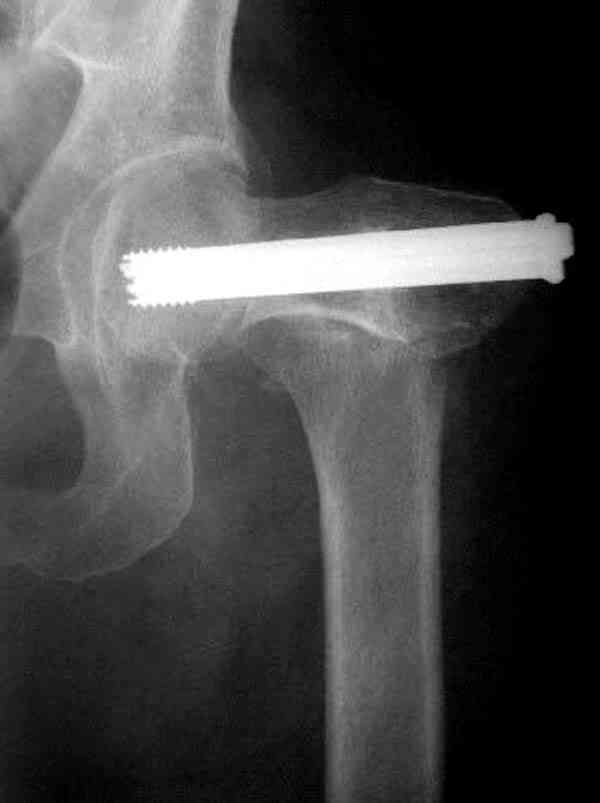

Не ради критики, но меня заинтересовал предложенный доктором Матвеевым хирургический приговор - профилактика несовершенного перелома шейки у пожилых армированием.

В идеале для профилактики рефрактуры шурупы надо вводить не больше, чем под 130 градусным углом и не ниже уровня малого вертела.

Насчет биомеханических преимуществ одного шурупа тоже возникает вопрос. Если придерживаться канонов механики, для перелома шейки необходимо 3 паралельных шурупа, расположенных ближе к кортикальному слою шейки.

Здесь случай перелома из-за ослабления латерального кортекса через 3 недели после операции на шейке. Шурупы были установлены под большим углом, слабый латеральный кортекс не выдержал нагрузку.